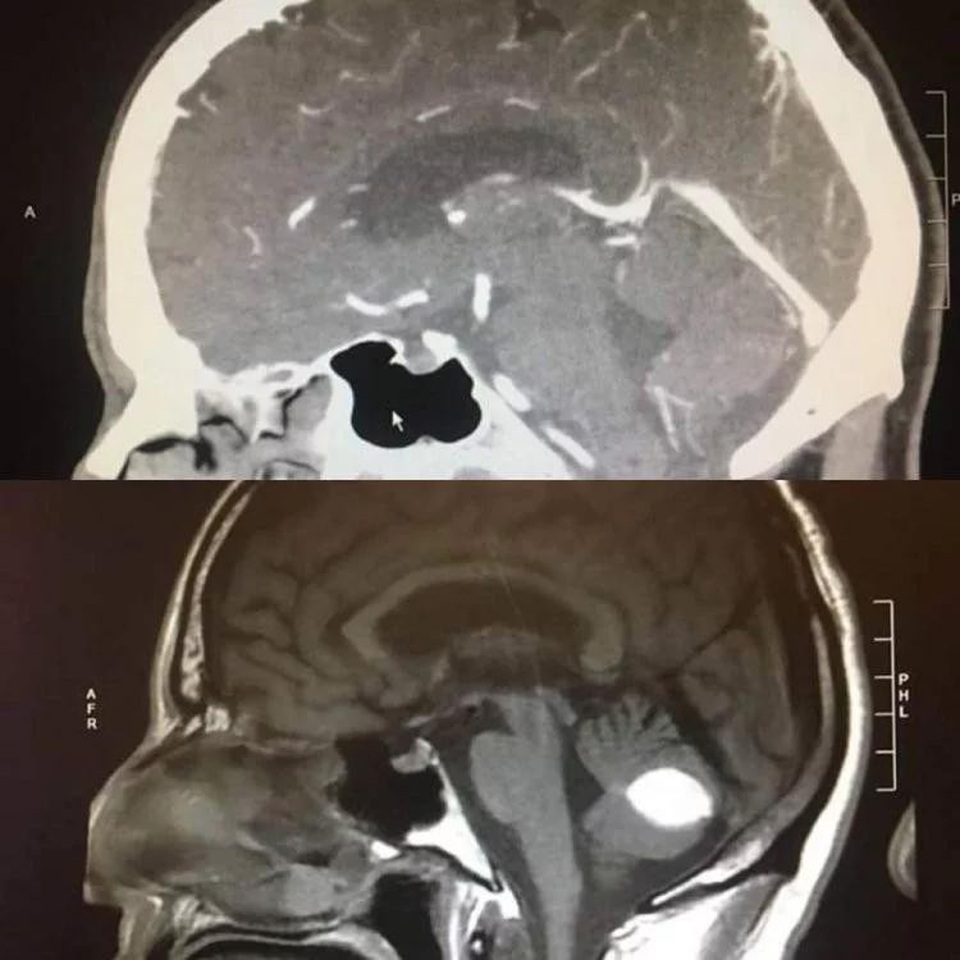

Một chuyên gia thần kinh ở Đại học California, San Francisco, kết luận rằng anh bị chảy máu não trong khi bác sĩ X-Quang thì lại thông báo là anh bị u não dựa trên kết quả chụp cắt lớp nhận được. Cả hai lời chẩn đoán đều yêu cầu anh phải tiến hành phẫu thuật não rất nguy hiểm.

Thế nhưng chỉ một ngày trước khi phẫu thuật, anh được chụp cắt lớp lần nữa và lần này thì não anh hoàn toàn bình thường, không có một khối u nào cả.

Các bác sĩ đã nhờ Paul tiếp tục tham gia nghiên cứu để họ có thể tìm hiểu xem chuyện gì đã xảy ra. Tại sao khối u trắng trong phim chụp lại biến mất một cách bí ẩn như vậy?